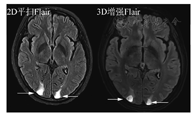

另外,DWI由于非常有诊断价值和扫描时间短,建议始终放在平扫序列里。而注射造影剂前的平扫中,只扫Flair序列,T2放在增强后扫描。优化标准中,主要增加了DSC灌注扫描(可能对鉴别肿瘤复发和放射性坏死有用)、增强后Flair(显示软脑膜转移病变较常规增强T1MRI效果好)以及增强后长时间延迟扫描(60~105 min,以期显示小病灶)。关于增强后Flair序列,对于脑膜转移的增强显示能力已被认可。对于脑实质内的转移瘤病灶,并不能增加诊断信息,但是对于靠近皮质的表浅病灶,显示能力超过常规增强T1,详见图3、图4。不同MR扫描机的序列名称不同,但序列的本质一致。

关于软脑膜转移,常规增强T1SE序列常难以发现,GRE序列由于血管增强效应,会导致脑沟内多发的条状或者点状高信号,即高估效应,带来假脑膜转移瘤征象。近年来,增强后Flair序列在显示脑膜转移瘤方面显示出一定优势,尤其在一定时间的延迟后,更可以确认脑膜转移的有无,从而准确评估预后和制定治疗决策。